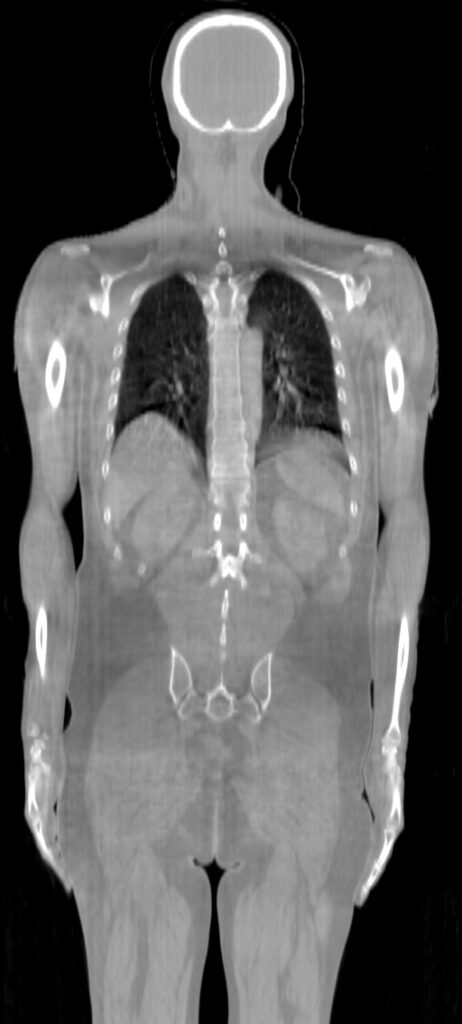

ClearRT® Images

Imaging Information

ClearRT®

Protocol

Whole body-mediumFOV 50cm

Scan Length

84 cm / 1 min